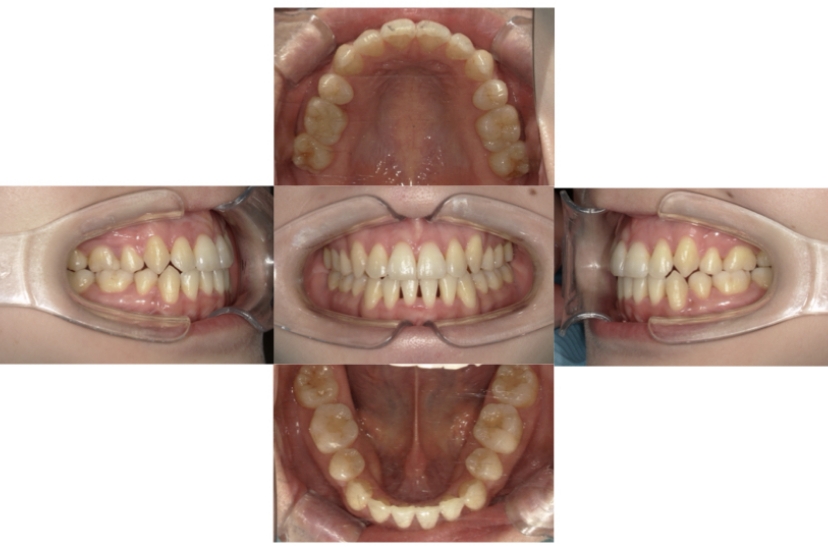

症例4

下顎前突、叢生

抜歯

ブラケット矯正

上下顎叢生、反対咬合(上下の前歯のガタガタ、若干受け口)のケースです。

装置はラビアル(上下表側)で、上下顎の小臼歯を4本抜歯を行っています。抜歯したスペースを使って、上下の叢生改善と前歯の受け口の改善を行っています。

主訴 前歯のガタガタを治したい。

年齢・性別 45歳 女性

お住まいの地域 神奈川県川崎市

治療方針 抜歯スペースを利用して上前歯の叢生(ガタガタ)の改善と受け口の改善

抜歯部位 上顎左右第一小臼歯、下顎左右第二小臼歯

使用装置 ラビアル(上下表側)、顎間ゴム

治療期間 2年6か月

治療回数 20回

リテーナー クリアリテーナー

BEFORE

AFTER